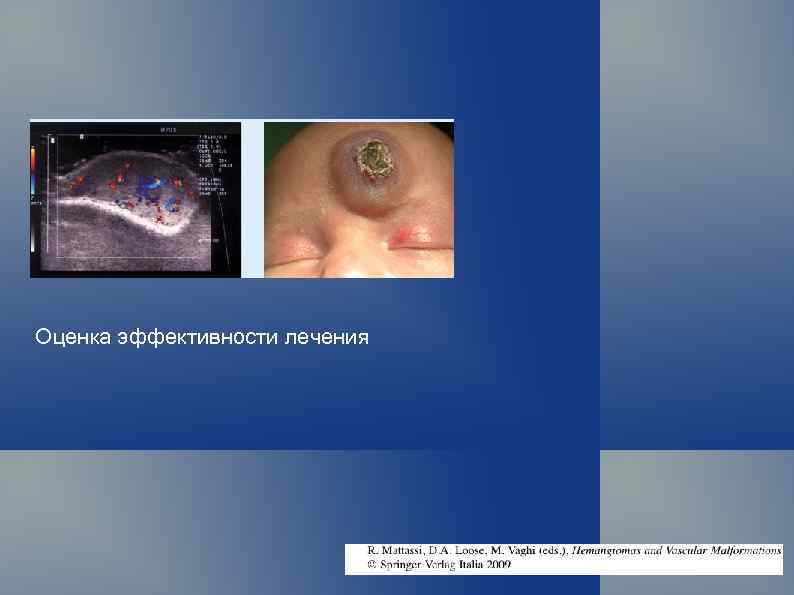

Оценка эффективности лечения

Эффективность лазеротерапии. Не вместо операции, а для того, чтобы избежать операции.